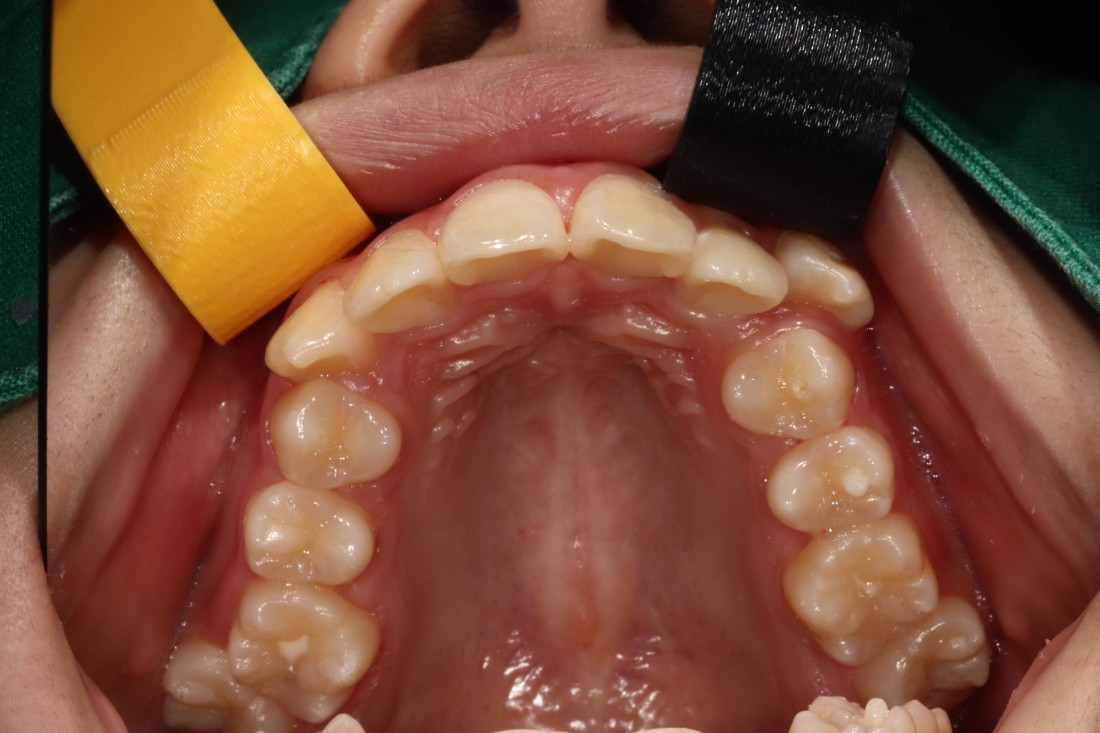

덧니는 과거에는 귀여운 이미지를 줘서

선호하기도 하였지만,

요즘은 고른 치열을 만들어서

세련된 외모를 완성하는 것이

필수 트렌드가 되고 있습니다.

광주 교정치과에서는

3차원 105항목 정밀검사를 통해

발치교정 / 비발치교정 을 포함하여

정확한 치료계획을 세우고 있습니다.